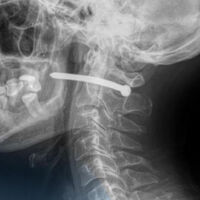

В Петропавловске 51-летний мужчина обратился в городскую больницу скорой помощи с ранением за ухом. Как выяснилось, во время ремонта он случайно получил травму — в него выстрелил гвоздь из пневматического пистолета.

Рентген показал, что металлический предмет прошел буквально в миллиметрах от шейного отдела позвоночника. Медики отметили, что мужчине невероятно повезло — жизненно важные органы и сосуды не были повреждены.

Хирурги извлекли гвоздь, тщательно обработали рану и наложили швы. После процедуры пациента отпустили домой с рекомендациями. Врачи напомнили, что любые травмы шеи представляют серьезную опасность, ведь в этой области проходят крупные артерии, нервы, дыхательные пути и спинной мозг.